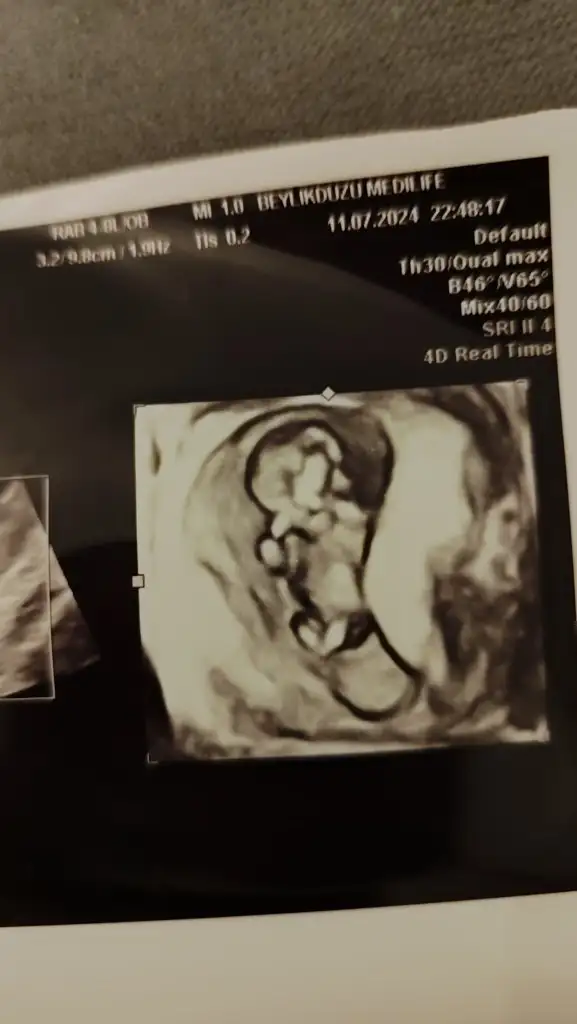

Az önce çekildik. 12+0 ız. Cinsiyet tahminleri nedir arkadaşlar?

• IMG_20240711_222412.webp

IMG_20240711_222412.webp

18,1 KB · Görüntüleme: 71

• IMG_20240711_222407.webp

IMG_20240711_222407.webp

17,7 KB · Görüntüleme: 75

• IMG_20240711_222357.webp

IMG_20240711_222357.webp

18 KB · Görüntüleme: 65